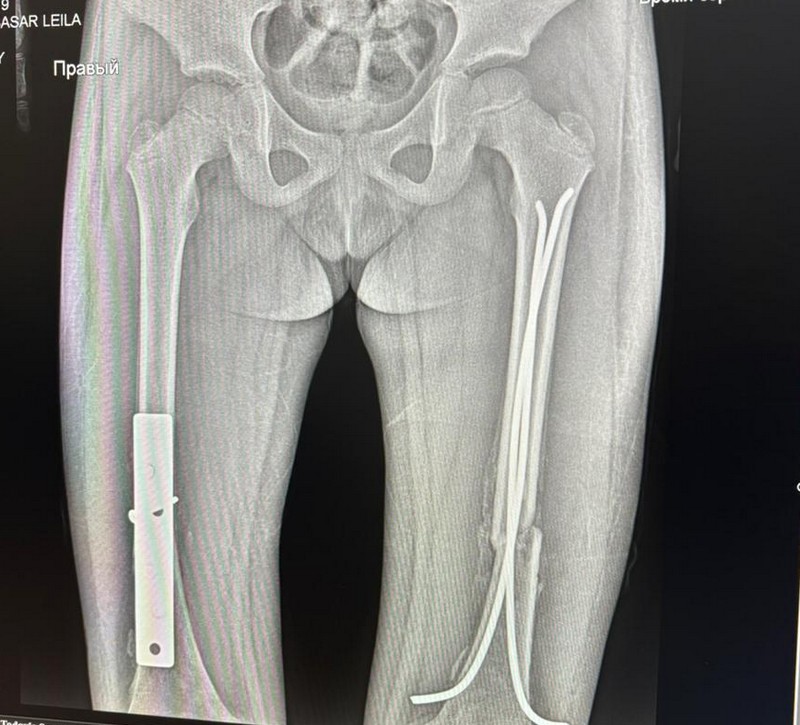

Девочка получила крайне тяжелые травмы: были сломаны челюсть, кости ладони левой руки, повреждены ребра, пострадали легкие, выбиты зубы, по всему телу - открытые раны.

Самым тяжелым оказался перелом бедренной кости - она была переломана пополам и раздроблена.

Кроме этого, впереди операции на обе ноги: извлечение металлических конструкций и коррекция правой ноги, которая неправильно срастается.